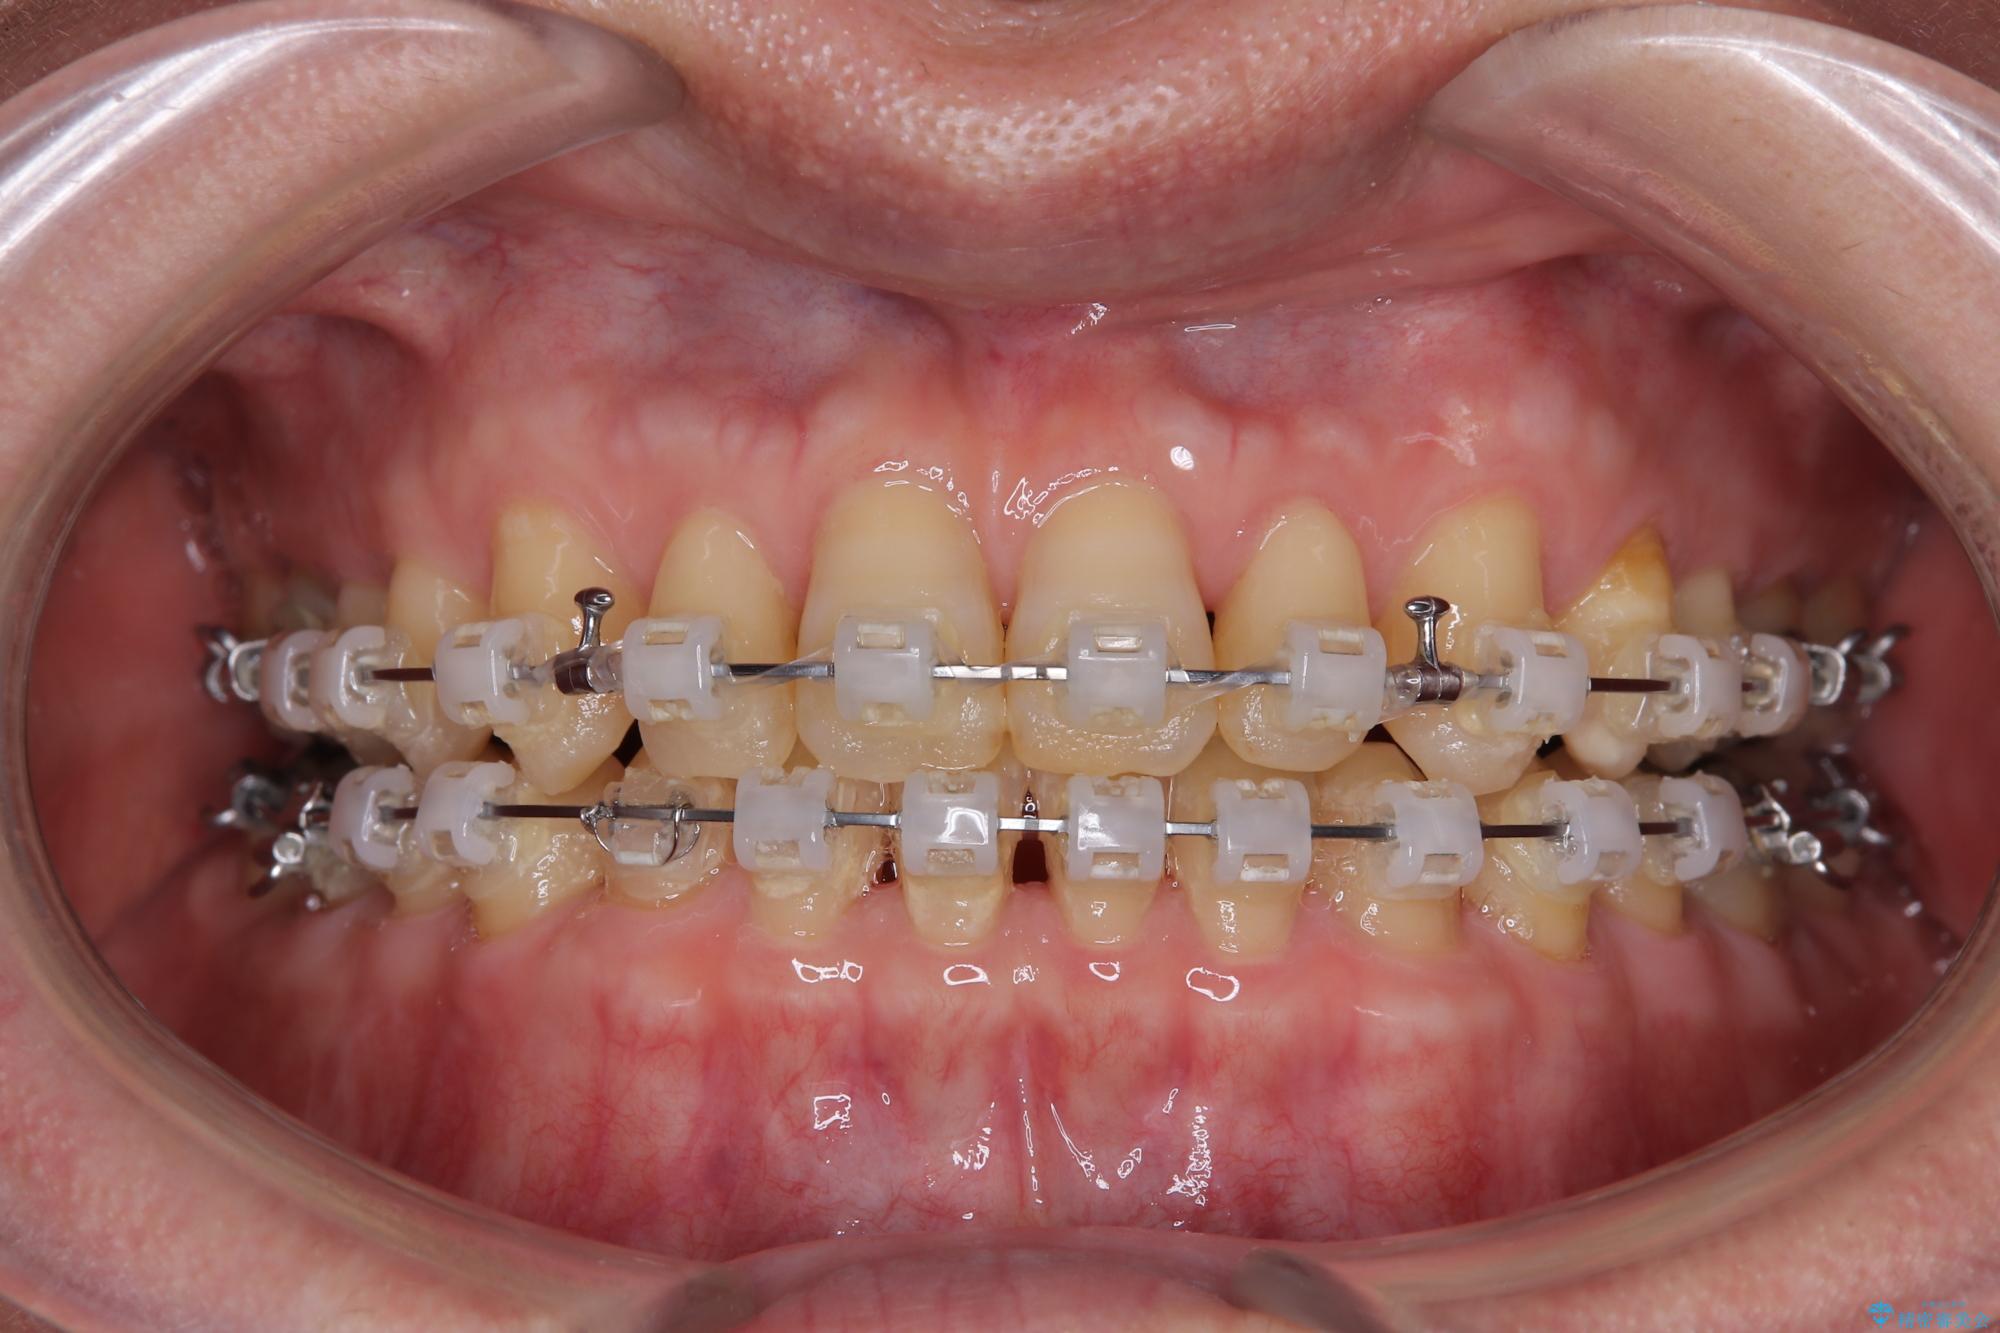

- 矯正装置

- クリアブラケット

- 治療期間

- 1年6ヶ月